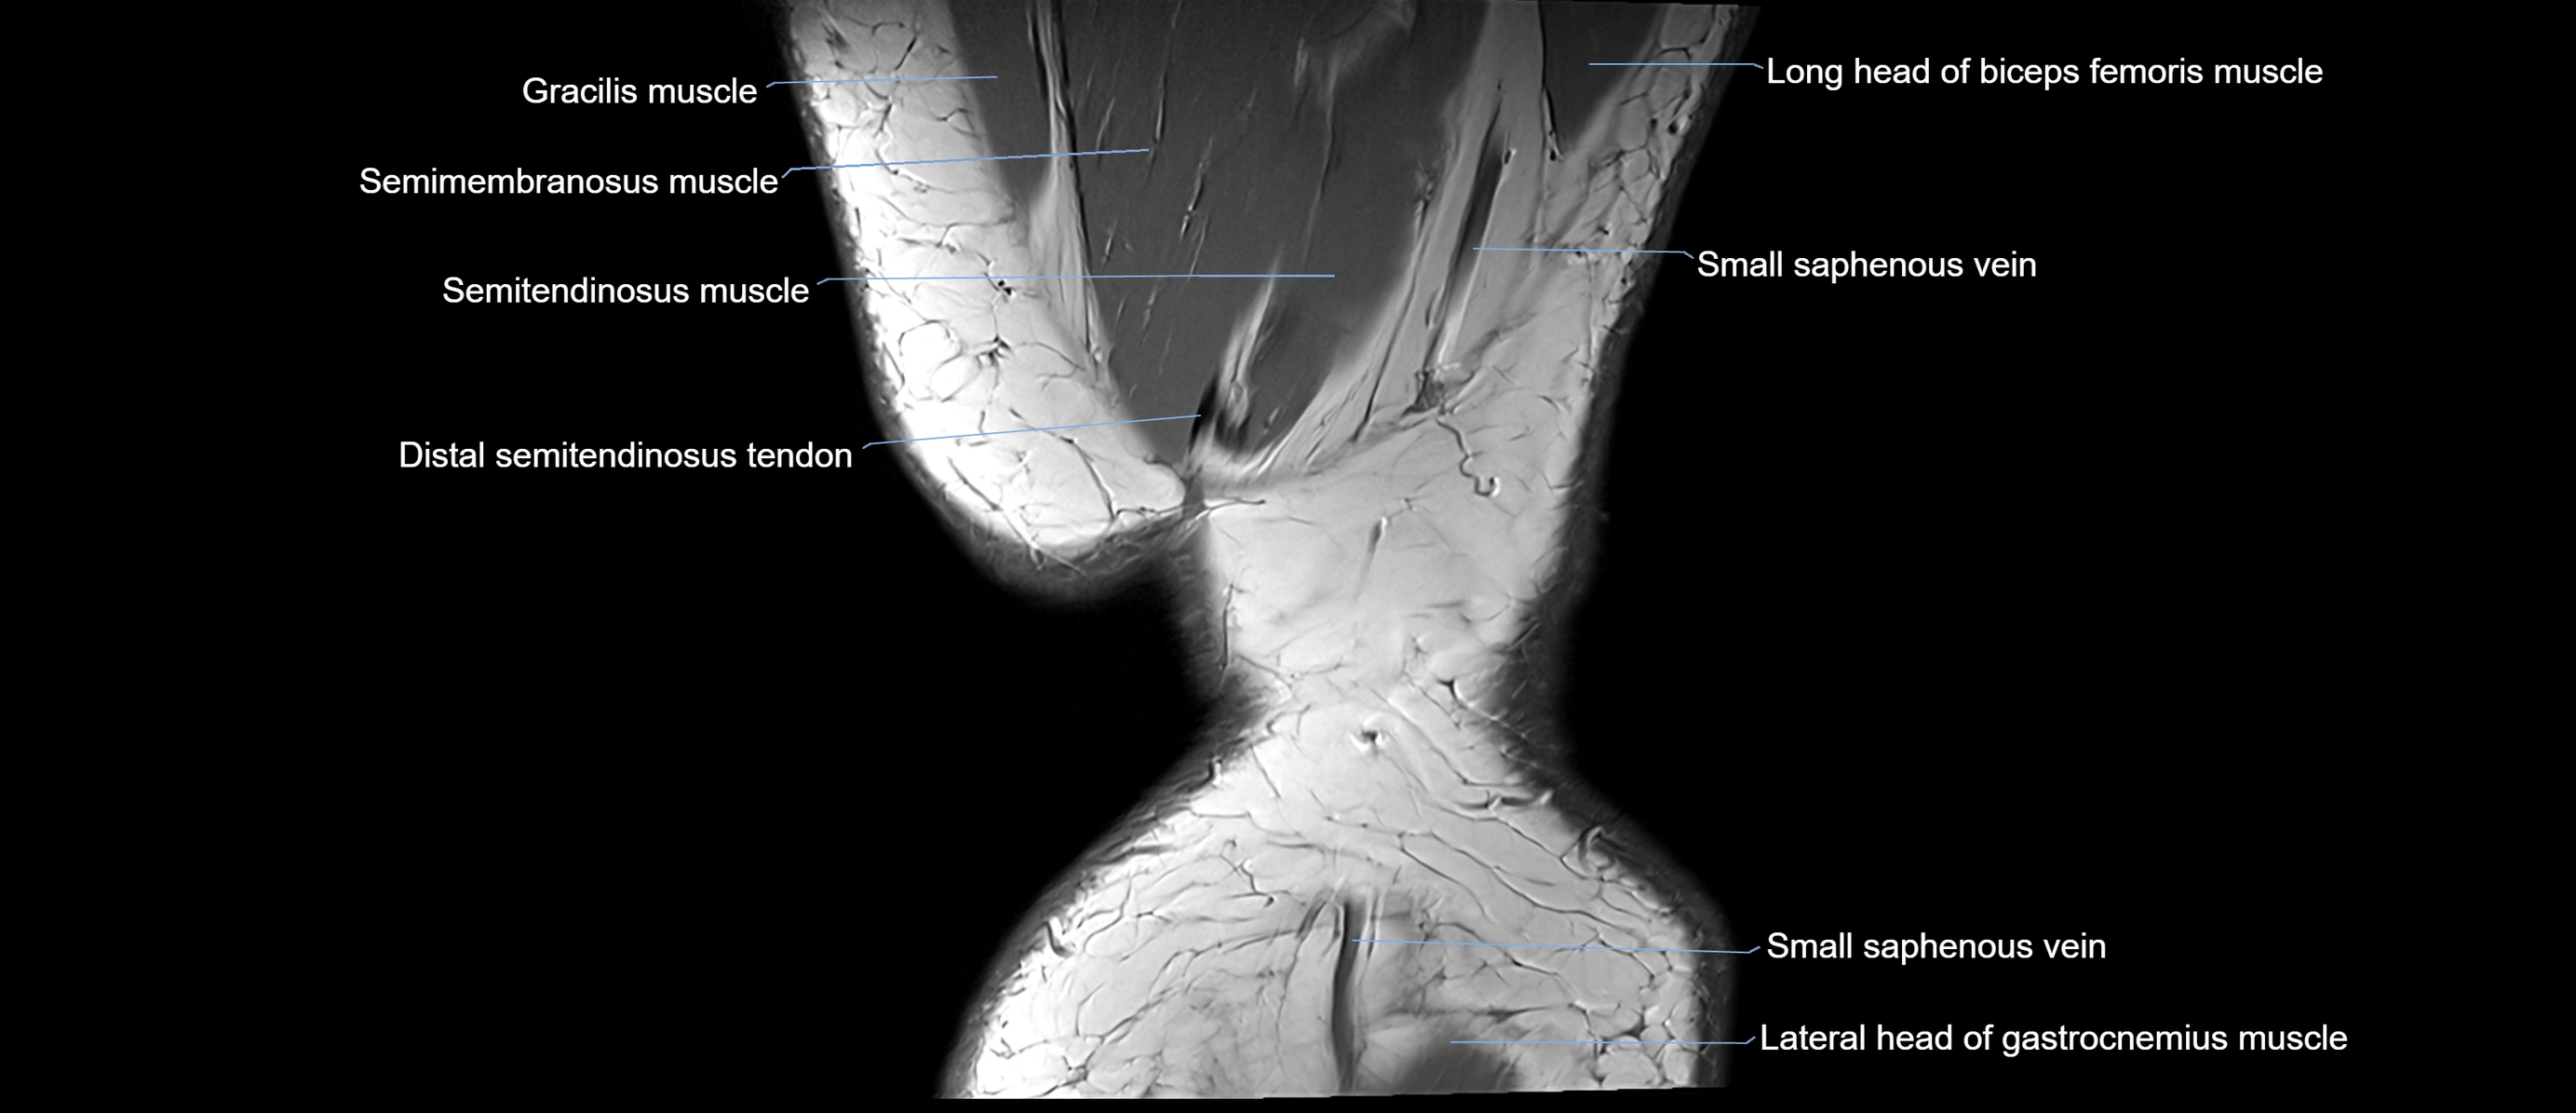

- Gracilis tendon (Distal)

- Lateral head of gastrocnemius muscle

- Semimembranosus muscle

- Semitendinosus muscle

- Small saphenous vein